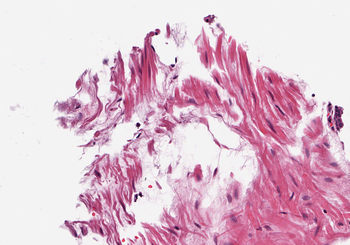

4.1 Quality of Color Normalization

A qualitative and quantitative comparison of the SPCN algorithm with other color normalization techniques is described in Vahadane et al. (2016), and justifies its choice as a starting point in this work. In Figure 2, we compare the performance of the original SPCN to our improved version on three challenging examples of source images taken from TCGA. On Image (a), the original SPCN exhibits swapping of stain color basis due to the presence of significant blue components in both stains. Our proposed improvement to compare the difference of red and blue components avoids this error. Image (b) illustrates that in cases where one stain dominates, SPCN can lead to a color tint in the intermediate whitespace. Our algorithm avoids this by estimating a channel-wise maximum pixel intensity. Image (c) shows an image with a significant background portion, which leads to a strong tinge in the background after normalization in an extreme case, which is also handled well in our results by estimating the maximum intensity for each channel separately.